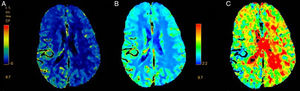

Two patients showed normal perfusion, with no asymmetries in CBV, CBF, or time to peak (Tmax). The most frequent finding in the rest of the sample was longer time to peak (Tmax), with varying CBF and CBV (Figs. 1–3).

Perfusion CT scan from patient 7. Right hemisphere syndrome (NIHSS score: 6). (A) Decreased CBF in the right hemisphere. (B) Longer Tmax at a similar location in the cortex. Changes do not clearly correspond to a specific vascular territory. CT-angiography revealed no large-vessel occlusion.

Perfusion CT scan from patient 9. Left hemisphere syndrome (NIHSS score: 10). (A) Decreased CBF in the left parieto-occipital area. (B) Decreased CBV in the left parieto-occipital area. (C) Longer Tmax at a similar location in the cortex. Changes do not clearly correspond to a specific vascular territory. CT-angiography revealed no large-vessel occlusion.